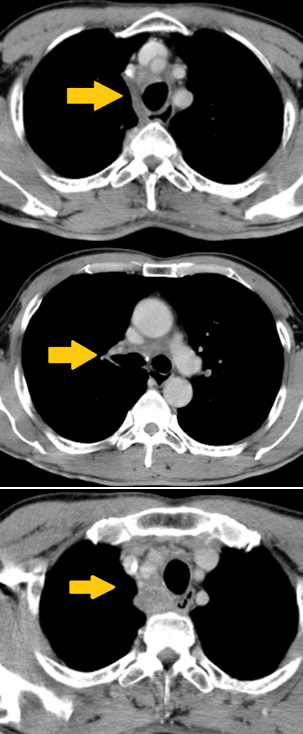

- Chụp cắt lớp vi tính lồng ngực:

Hình 1. Hình ảnh khối lớn trong trung thất giữa KT 81x63x70mm, xu hướng xâm lấn màng phổi trung thất và nhu mô phổi phải vùng rốn phổi, chèn ép bờ phải khí quản, nhiều hạch trung thất kích thước lớn nhất 34x28mm (mũi tên màu đỏ), nốt đặc thùy trên phổi phải theo dõi thứ phát.